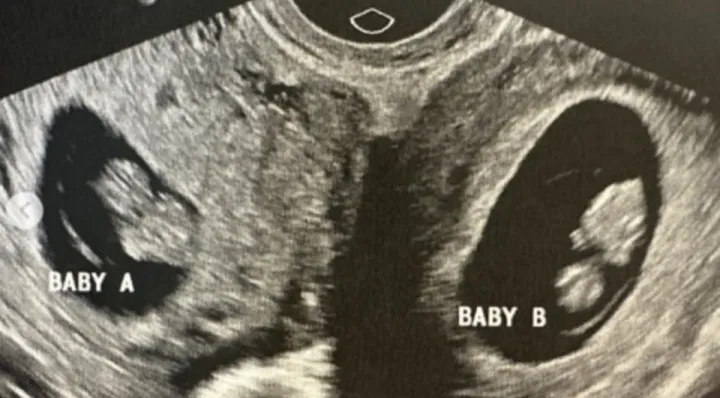

Ультразвуковое изображение двух маток с плодами в них. Ультразвуковое изображение двух маток с плодами в них.© doubleuhatchlings